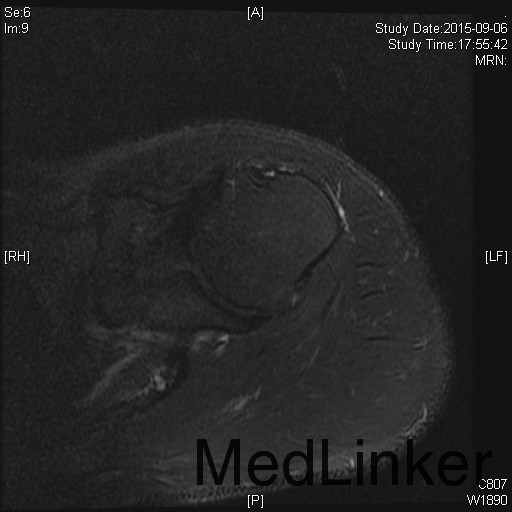

主诉:左肩扭伤后疼痛不适伴弹响10余年,加重3月。 现病史:患者10余年前扭伤左肩关节后出现疼痛不适等症状,伴活动时弹响,以运动时明显。患者当时未重视,未就诊。10余年来患者左肩疼痛不适症状反复发作,曾至外院行局部理疗、小针刀等保守治疗,效果不佳。3月前患者再次扭伤左肩,当即感觉左肩症状加重。来我院就诊,我院行MRI检查示:左肩盂唇信号异常及肱二头肌长头肌腱信号异常。

1、诊断:左肩创伤性前不稳定,左肩SLAP损伤。 2、治疗:全麻下行左肩关节镜下前盂唇、上盂唇修补术。